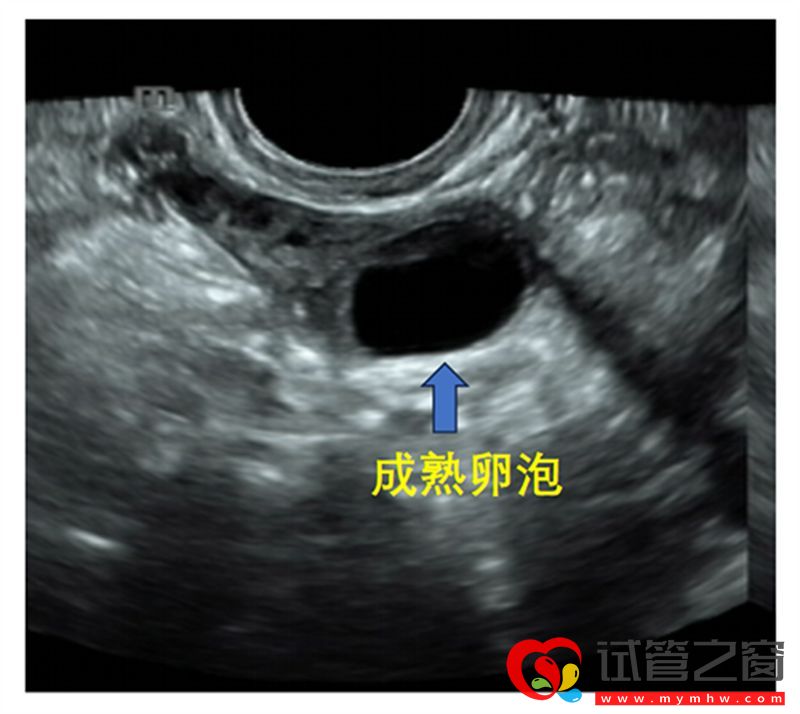

B超監測成熟卵泡

成熟卵泡(月經周期14天左右):卵泡直徑達到18-25mm時,外形飽滿呈圓形或橢圓形,內壁薄而清晰,位置移向卵巢表面并向外突出,如果卵泡一側內壁上探及卵丘(出現率約20%),表現為細小點狀高回聲 ,意味著排卵過程將在24小時內開始。